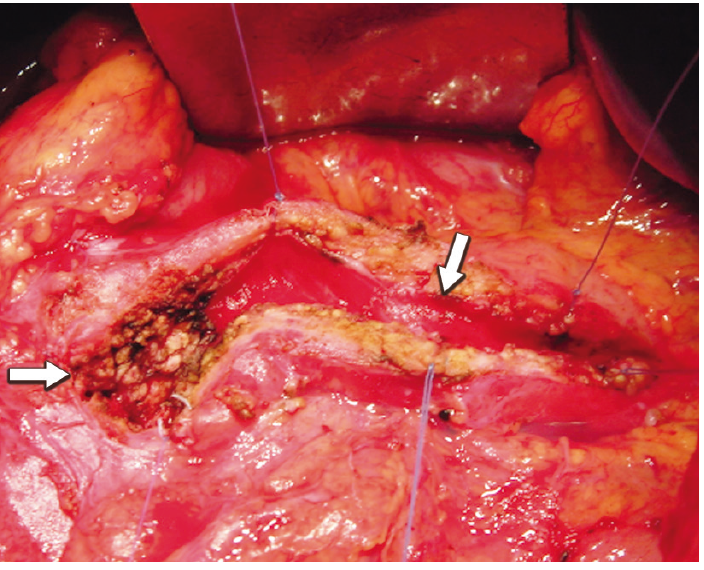

Figura 3. Imagen intraoperatoria de la cavidad única terminada, con la resección

ojival en saca bocado a nivel de la cabeza en continuidad con el conducto de Wirsung destechado del cuerpo y

cola.

La resección de la cabeza se realiza en forma parcial, conservando un margen de tejido pancreático de aproximadamente 1 cm sobre el marco duodenal y la vena porta. A la cavidad resultante en la cabeza se la comunica con el conducto pancreático principal del cuerpo y cola, previamente destechado, transformándolo en una estructura única. El procedimiento finaliza con la anastomosis de la cavidad labrada a lo largo de todo el páncreas y el yeyuno (Figuras 1 y 3).